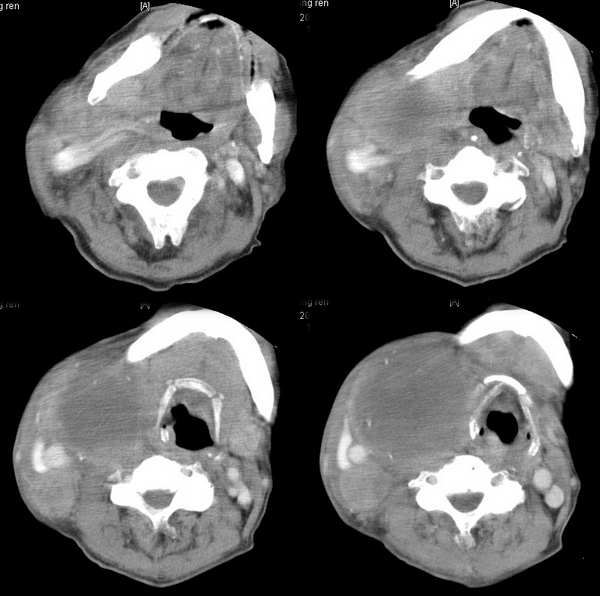

男,74岁,甲状腺肿30余年。现右颈部出现新肿块,疼痛,感乏力。

右颈部巨大软组织肿块影,范围较广,上至下颌角,下至颈静脉切迹。其最大层面位于右侧甲状腺区。肿块密度不均,其中有坏死液化区和班片状钙影,增强扫描见肿块实质区有强化。邻近结构挤压移位,部分结构侵蚀破坏,右侧多个颈深淋巴结肿大。两肺弥漫分布小结节影,以胸膜下为主,其大小不等,边缘光整。右侧胸壁亦见软组织结节影,纵隔多个淋巴结肿大及两侧锁骨上淋巴结肿大。

意见:右侧甲状腺癌并两肺、胸壁、纵隔淋巴结、颈深淋巴结、锁骨上淋巴结等广泛转移。